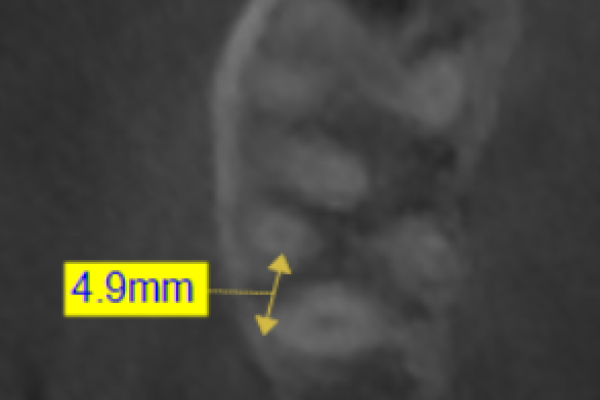

Implantes de 4,5mm de longitud utilizados en atrofia ósea en altura (hueso residual ≤ 4,5m). Estudio retrospectivo

Implantes de 4,5 y 5,5 mm longitud insertados de forma directa en elevación crestal con hueso autólogo unido al Endoret-PRGF en alturas óseas residuales de 2-3 mm: estudio retrospectivo

Implants of 4.5 and 5.5 mm length inserted directly in crestal elevation with autologous bone attached to PRFG-Endoret in residual bone heights of 2-3 mm: retrospective study

Elevación de seno transcrestal con inserción de implantes ultracortos de 4,5 mm de longitud en zonas maxilares posteriores con hueso residual menor o igual a 3 mm de altura